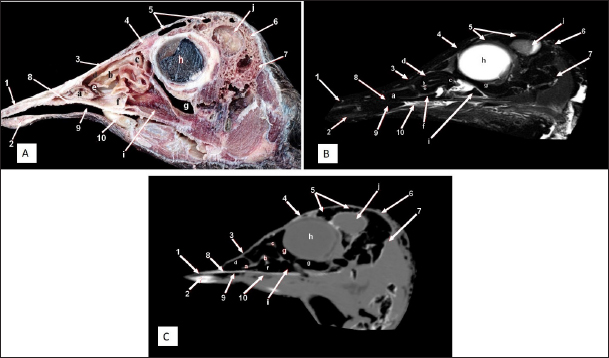

Fig. 3. Sagittal cross section of the adult ostrich head—level 2. A) Photograph of a paramedian sagittal anatomical section (medial view). B) MRI and C) computed tomography images showing: 1- Os premaxillare, 2- Os dentale, 3- Os nasale, 4- Processus. frontalis, 5- Frontal sinus, 6- Os parietale, 7- Os temporalis, 8-Palate, 9- Oral cavity, 10- Tongue, a- Rostral nasal concha, b- Middle nasal concha, c- Caudal nasal concha, d- Dorsal nasal meatus, e- Middle nasal meatus, f- Ventral nasal meatus, g- Infraorbital sinus, h- Orbit containing eye ball, i- Choanal opening and j-Cranial cavity.

Fig. 4. Sagittal cross section of the adult ostrich head—level 3. A) Photograph of a paramedian sagittal anatomical section (medial view). B) MRI and C) computed tomography images showing: 1- Os premaxillare, 2- Os nasale, 3- Frontal sinus, 4- Processus.frontalis, 5- Cerebral hemisphere, 6- Os frontalis, 7- Os dentale, 8- Oral cavity, 9- Tongue, a- Middle nasal concha (rostral part), b- Middle nasal concha (caudal part), c- Ventral nasal meatus and d- Vomer.

The nasal conchae exhibited in the MRI images as bright (high or hyperintense signal intensity) to gray (low or hypointense signal intensity) structures that could be divided into three parts: rostral, middle, and caudal conchae, which correlated to the morphological examinations. In contrast, the nasal conchae could not be recognized clearly on CT images compared to those obtained after MRI (Figs. 25 B and C). The paranasal sinuses with other structures could be identified using both CT and MRI. The nasal septum and paranasal sinuses revealed a white bone border (high signal intensity), soft tissue was grey (low-to-intermediate signal intensity), and they contained black gas, so both the CT and MRI scans showed little signal intensity (Figs. 15B and C and 79B, C, E, F).